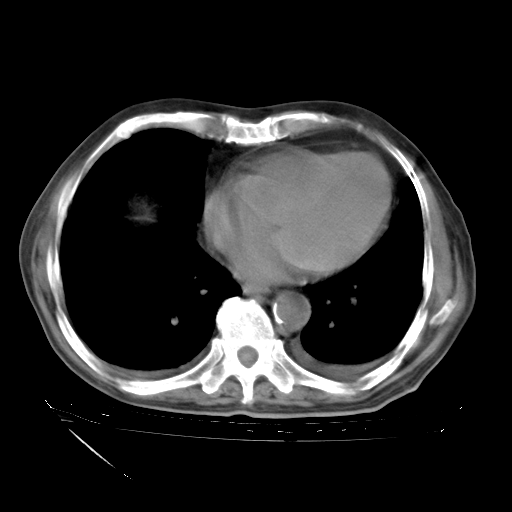

甲强龙80mg/日+抗结核治疗(异烟肼+利福霉素+乙胺丁醇)10天。复查肺部CT。

治疗10天肺部CT

补充下:5月9日胸部CT:似乎已见双下肺胸腔积液了,鉴于目前有下肢水肿,肝功示:白蛋白低,应注意多浆膜腔积液(漏出液可能大?),需注意!